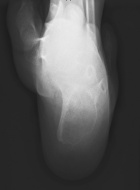

7 year old male who has had a six month history of left heel pain which was first noted with difficulty putting on his socks.

PMX- neurofibromatosis & scoliosis. Left foot pain is sharp, severe at times, constant in nature, worse with activity. Family describes the discomfort as worsening. It is made better with rest. He has no other history of trauma.